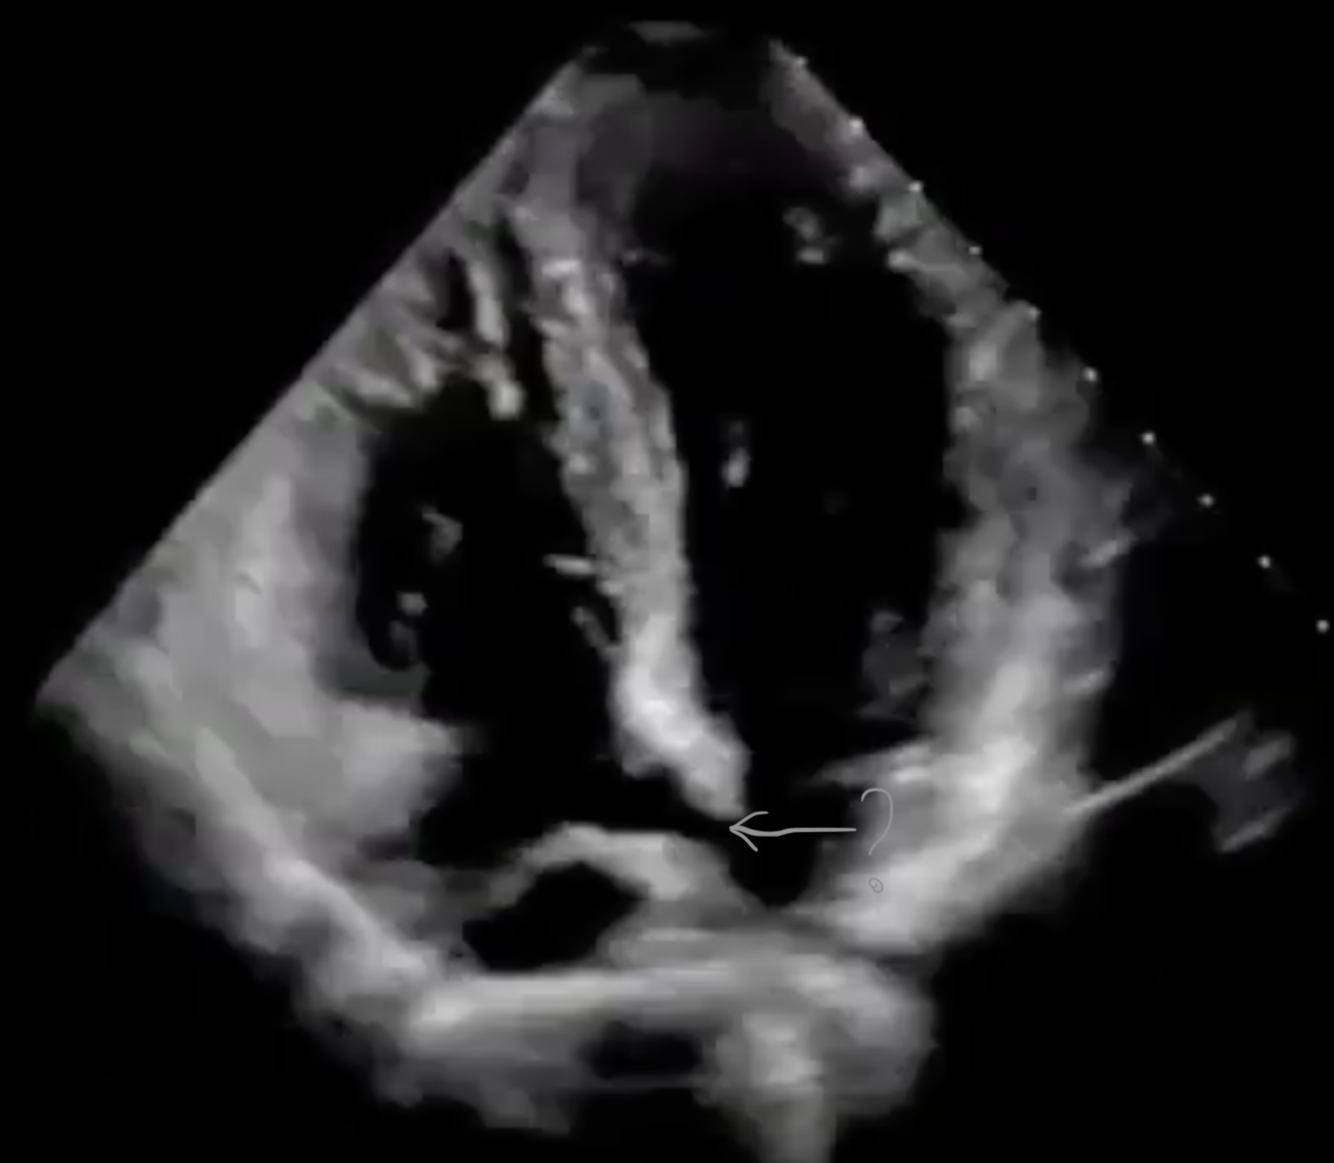

The arrow in this image is pointing to the:

A

coronary sinus

*aligning posterior in the A4C view allows you to demonstrate the coronary sinus. The coronary sinus collects blood from several smaller veins to form one vein and functions as the main vein of the heart. As seen in this image, the coronary sinus is the main cardiac vein that enters into the RA.